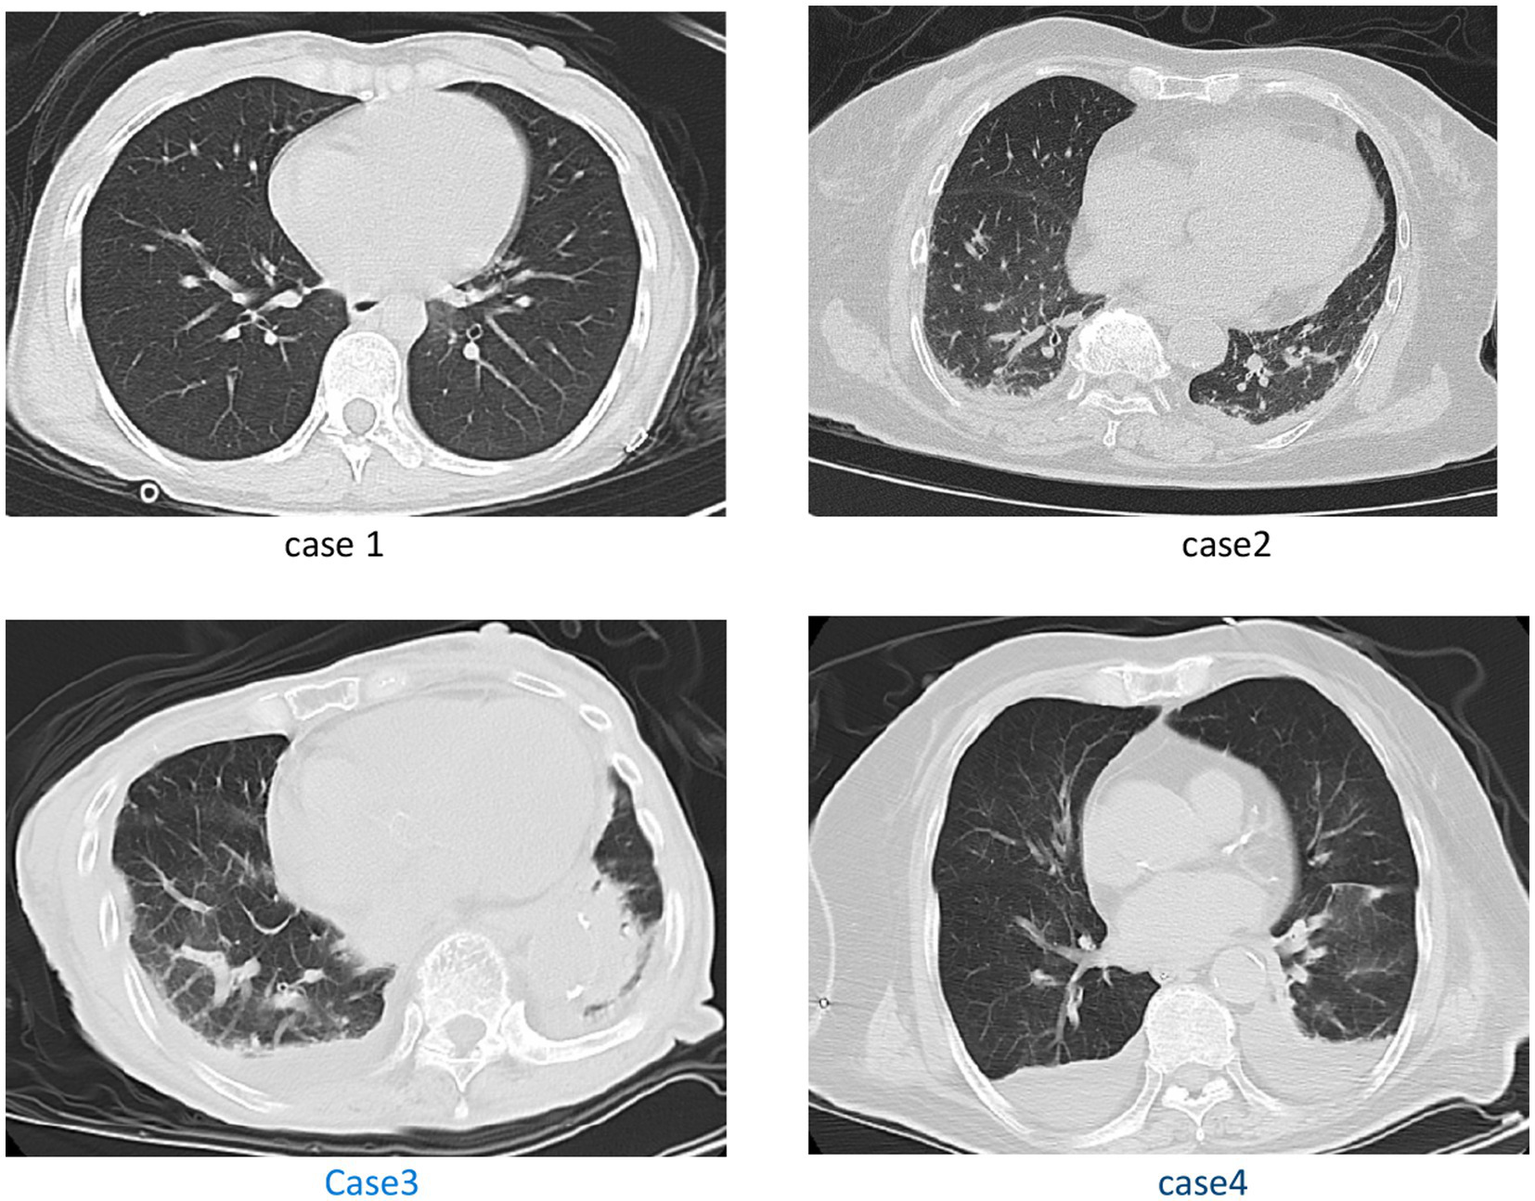

Figure 2

Case 1: with no significant positive chest CT signs. Case 2: pleural effusion, and thoracic cavity effusion. Case 3: scattered streak shadows in bilateral lung, scattered exudation in bilateral lung, pleural effusion. Case 4: multiple patchy high-density shadows in both lungs, and bilateral pleural effusion with adjacent lung tissue atelectasis.